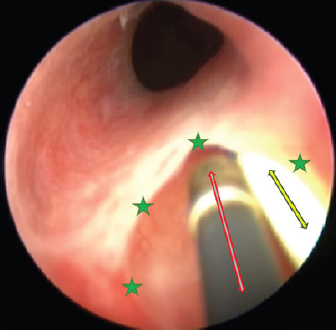

An orifice is found immediately where the urethra is formed; therefore, urine flows outward bypassing the urinary bladder and sphincter. Ectopy type is thought to be intramural due to visible thin mucous membrane partition between the bladder and ureter. It extends from the urethra to the anatomical ureter opening location. As seen in other ectopy cases, we observed a complex of pathologies: the urinary bladder was localized more caudally, and the urinary tract was shorter than usual (Fig. 2). Cystoscopy was performed with the instrument shown in Figure 3.

During the cystoscopy, a 1,000 ml injectable water bottle with disposable pressure infuser was used to expand and rinse the urinary tract. Findings were consistent with CT results. The urethra and bladder contained a mucous membrane tunnel which prevented the left ureter to open in a normal anatomic position. Instead, its orifice was shifted caudally straight into the urethra and not the trigone of the bladder.

Fig. 6. Cystoscopy picture where the ureteral membrane (see the green stars) is seen before cutting with the semirigid Karl Storz monopolar coagulating ball electrode (marked with a red arrow). A bright yellow 3 Fr guide catheter is seen on the right side of the picture (marked with a yellow arrow).